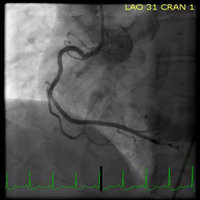

* Searchable database containing more than 30 videos (coronary angiograms, ventriculograms, and aortograms) of both common and rare findings in the cardiac catheterization lab

* Searchable database of over 65 images including hemodynamic formulas, tables, and figures

CathSource provides a detailed overview of important cardiac catheterization and angiography topics, incorporating educational images/videos as well as reviews of pertinent medical literature.

CathSource is the ideal application to assist you in understanding and recognizing cardiovascular pathology in the catheterization lab.